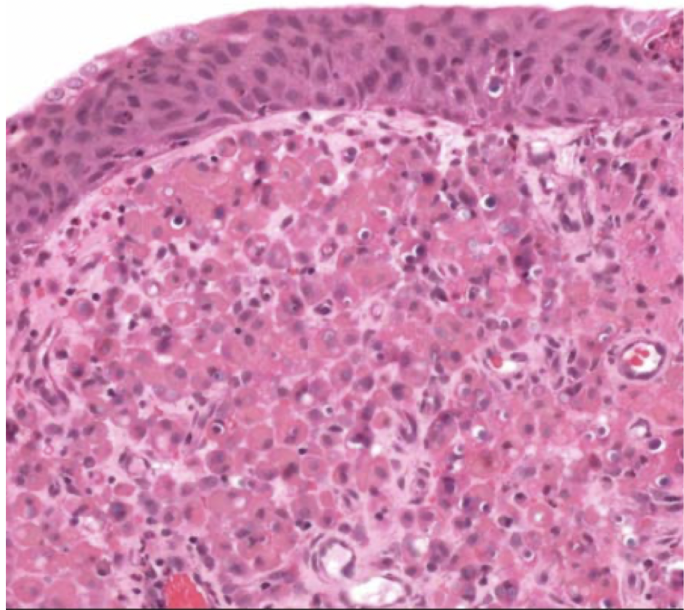

clear cell RCC

most common RCC

arise from proximal tubular epithelium

tendency to invade renal vein

von hippel-lindau syndrome (VHL)

buzzword: high HIF-1, increase VEGF and IGF-1

clear cell RCC

clear cell RCC

glycogen and lipid cytoplasm with rich vascular network